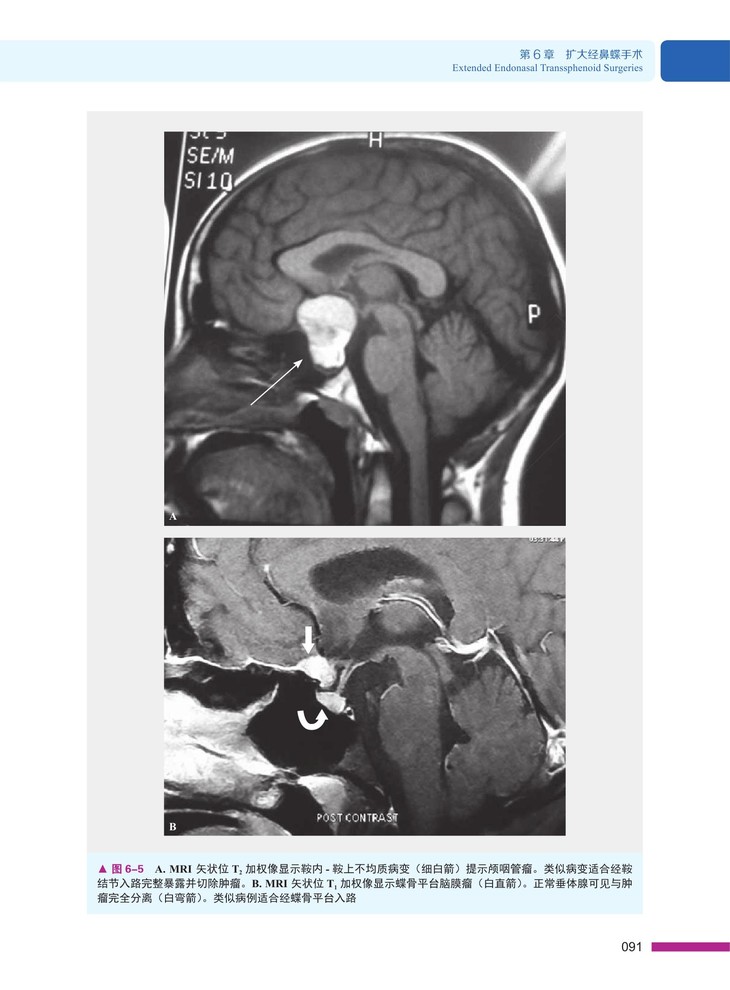

一、经蝶骨平台 / 经鞍结节入路

★ 内页插图 ★